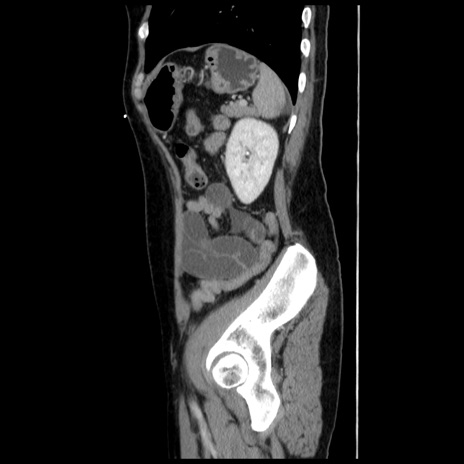

横断像

【症例】 50歳代女性

【主訴】 腹痛

【現病歴】前日生レバーを食べた。今朝に排便あり。 昼前に突然発症の腹痛を生じ、当院救急外来を受診した。

【既往歴】 子宮筋腫にてで子宮全摘後

【身体所見】 意識清明、腹部:平坦、軟、下腹部やや左を中心に圧痛・反跳痛あり、筋性防御あり

【データ】WBC 7800、CRP 0.07